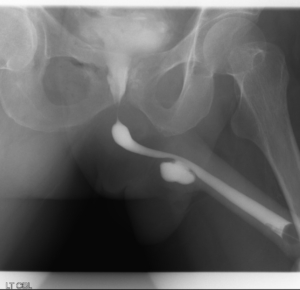

- Possible urethral stricture

- If a narrowing is found, a guidewire will be placed and urethra dilated

- If you have a urethral stricture, a guidewire will be placed and the narrowing dilated